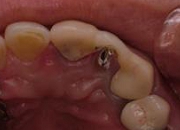

②当院で使用しているYAGレーザー(アストラテック)です.歯周ポケットの底部付近へレーザーのファイバーを無理なく安全に到達させるため,非常に細い径のファイバーを使用しています.これにより従来の装置と比較して治療がかなり容易になりました.

③歯の周囲に沿って,ぐるりと一周する要領でレーザーを単発照射していきます.照射そのものは5~10分程度で短時間に終了します.

必要な場合には,麻酔処置も可能です.

このレーザー治療を症状の改善に応じて数回行います(歯石やその他の起炎物質の除去も通法通りに行います).